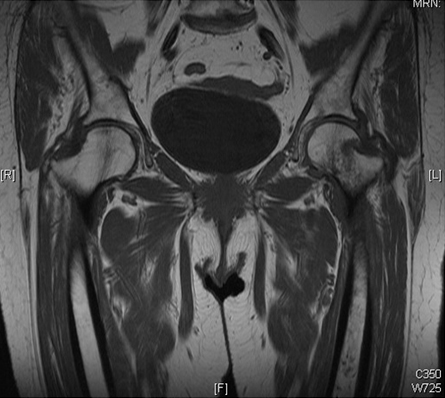

Al menos el 90% de las fracturas femorales proximales se identificarán en las radiografías.[52] Si el índice de sospecha de fractura de cadera es alto y la radiografía simple es negativa, debe solicitarse una exploración por TC o IRM (sin contraste).[50] La IRM tiene una sensibilidad más alta que las radiografías simples para la detección de fracturas ocultas de cadera y no depende del tiempo entre la lesión y el estudio.[50][53][54][Figure caption and citation for the preceding image starts]: Estudios por imágenes mediante resonancia magnética que muestra una imagen coronal que confirma una fractura intracapsular de la cadera izquierdaDe la colección de Bradley A. Petrisor, MSc, MD, FRCSC y de Mohit Bhandari, MD, MSc, FRCSC [Citation ends].